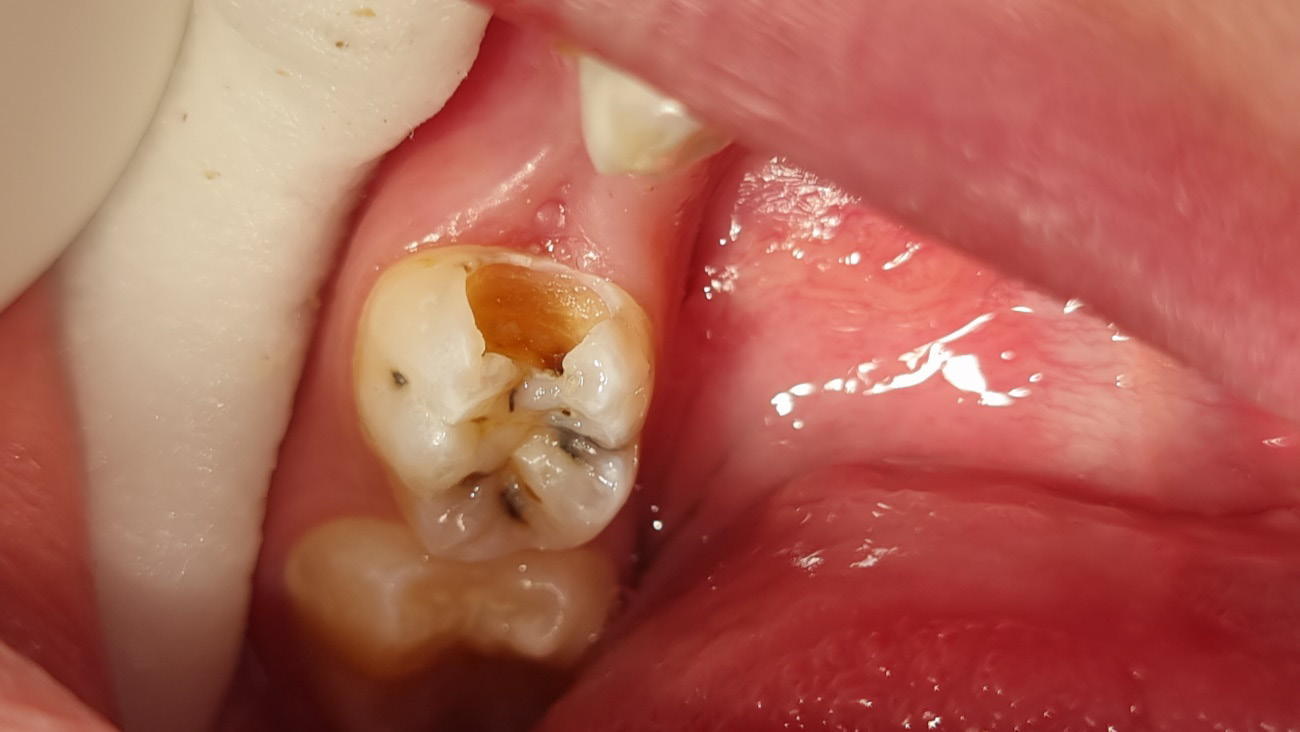

In the BRIX3000® group, the manufacturer’s guidelines were followed; BRIX3000® was applied to the cavity using a microbrush and left in place for approx. 2–3 min. Subsequently, the infected dentin that had dissolved was removed with a spoon excavator, without applying pressure or making incisions. In instances where the cavity was still occupied with infected dentin, the implementation of an additional layer of the agent might have been necessary (Figure 2). When sound dentin of the cavity was reached and all infected dentin was removed (Figure 3), the stopwatch was halted and the duration of the procedure was recorded in the case sheet, signifying the completion of the caries removal process.